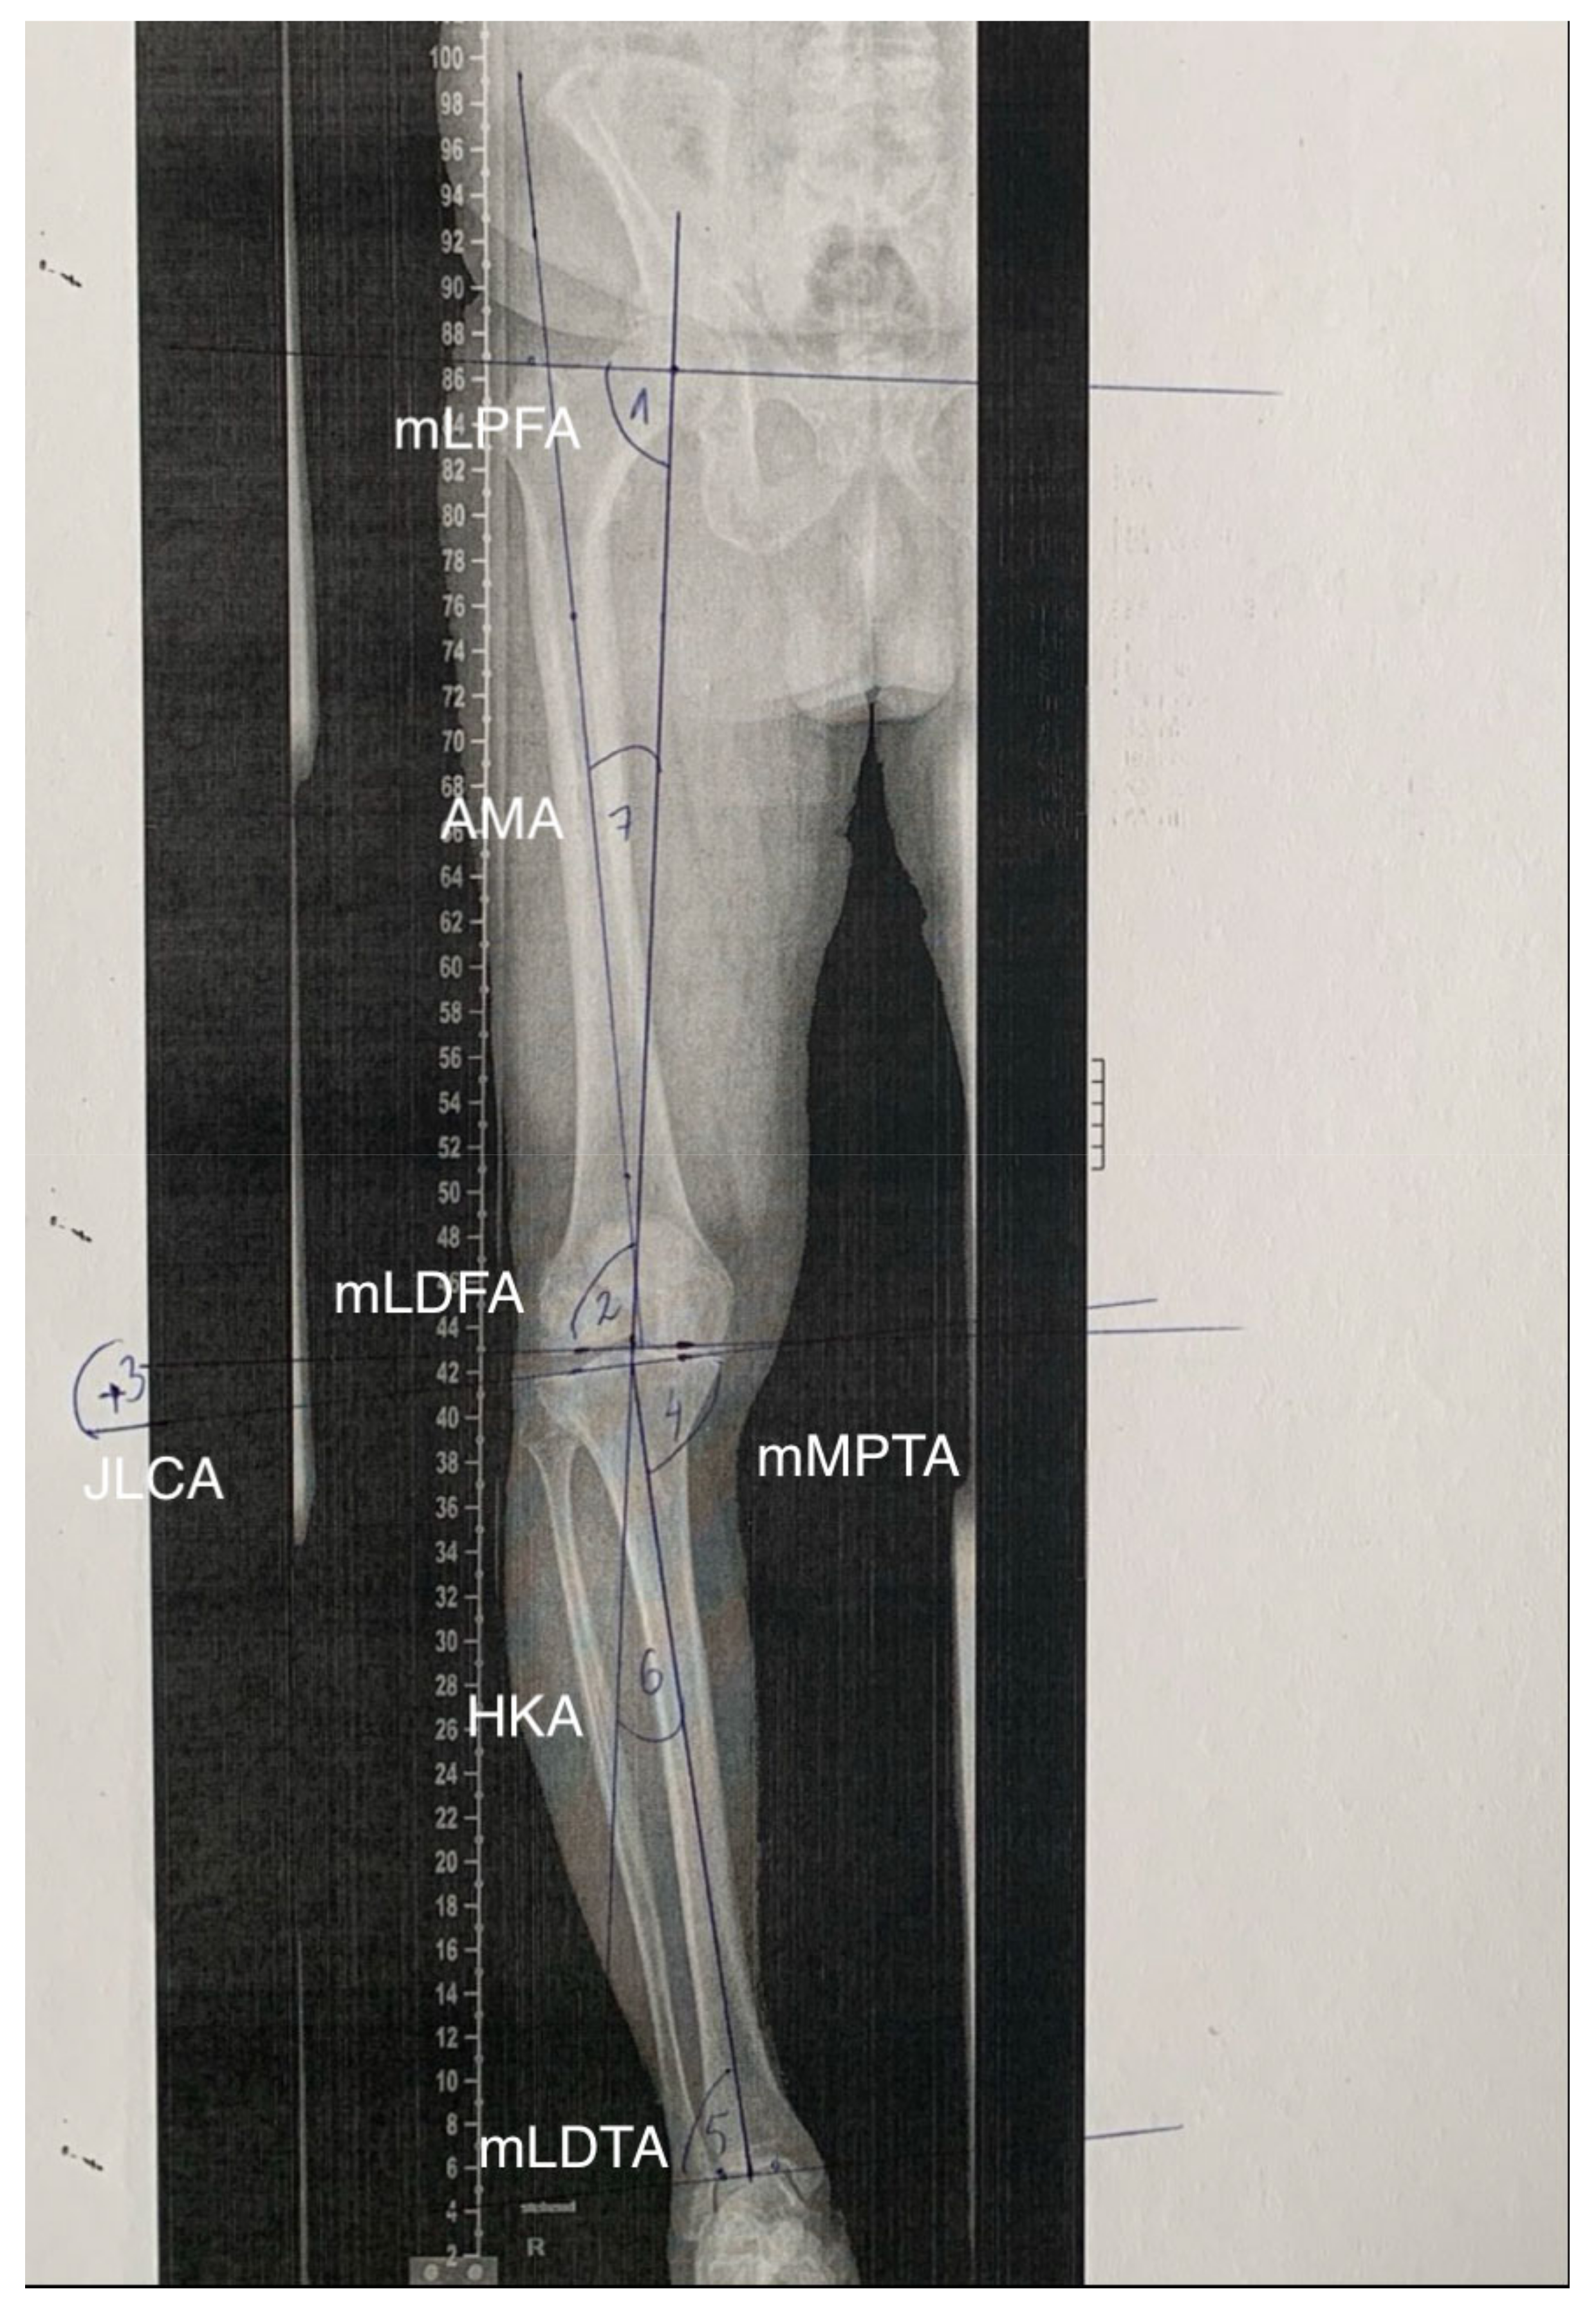

2.1. Manual Measurements

2.2. Software Measurements